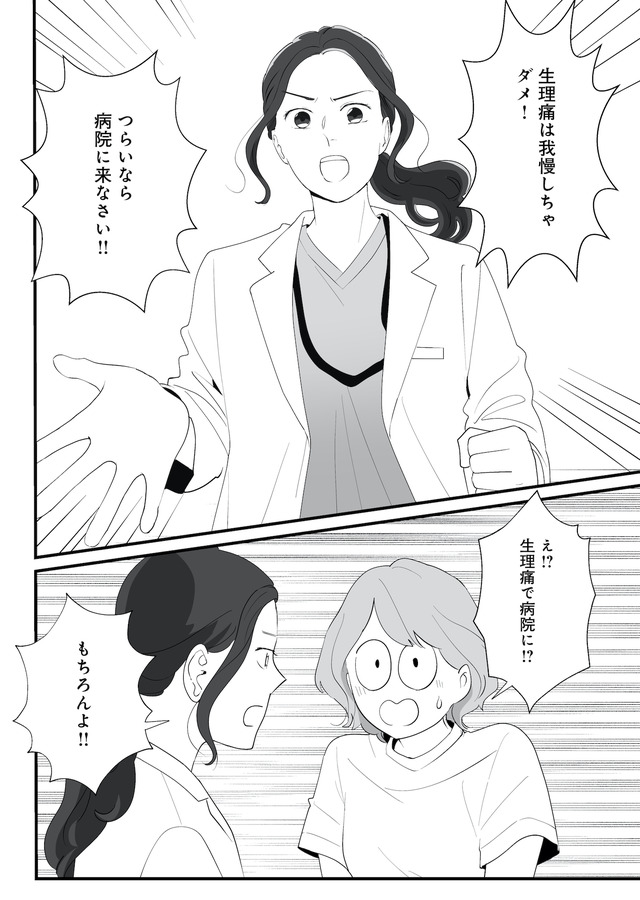

生理痛やPMSに苦しむあかり。通勤中、貧血で倒れて病院に運ばれたことをきっかけに、自分にあった生理用品や治療法を教えてもらうことに。

生理、吸水ショーツ、月経カップ、ミレーナ、ピル、卵子凍結、性のこと…

知ると知らないで大きく変わる! 自分のカラダとの向き合い方とは?

※本記事は、漫画・くゑ 、監修・高橋 怜奈 の書籍『産婦人科医に聞く わたしとカラダの選択肢』から一部抜粋・編集しました。